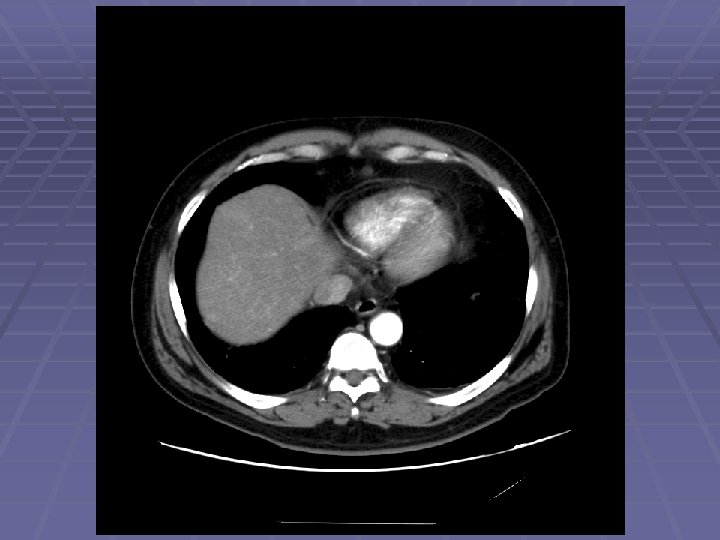

EUS Evaluation of Left Lobe of Liver